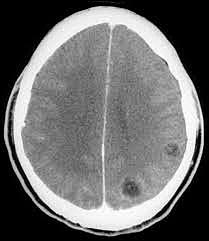

Estudios de neuroimagen

Método de elección para el diagnóstico de neurocisticercosis y para determinar el tipo de intervención terapéutica. Se realiza tomografía de cráneo simple y con contraste, la cual evidenció hidrocefalia aguda no comunicante y edema cerebral. Posteriormente se procede a colocación de válvula de derivación ventrículo-peritoneal, sin complicaciones con control tomográfico posterior donde se observó válvula de derivación.

Los estudios de imagen se complementaron con una resonancia magnética de cráneo donde se observó un quiste intraventricular anterior a la masa intertalámica con nódulo en su interior (escólex) y pared delgada bien definida, con lo que se estableció el diagnóstico de neurocisticercosis intraventricular.